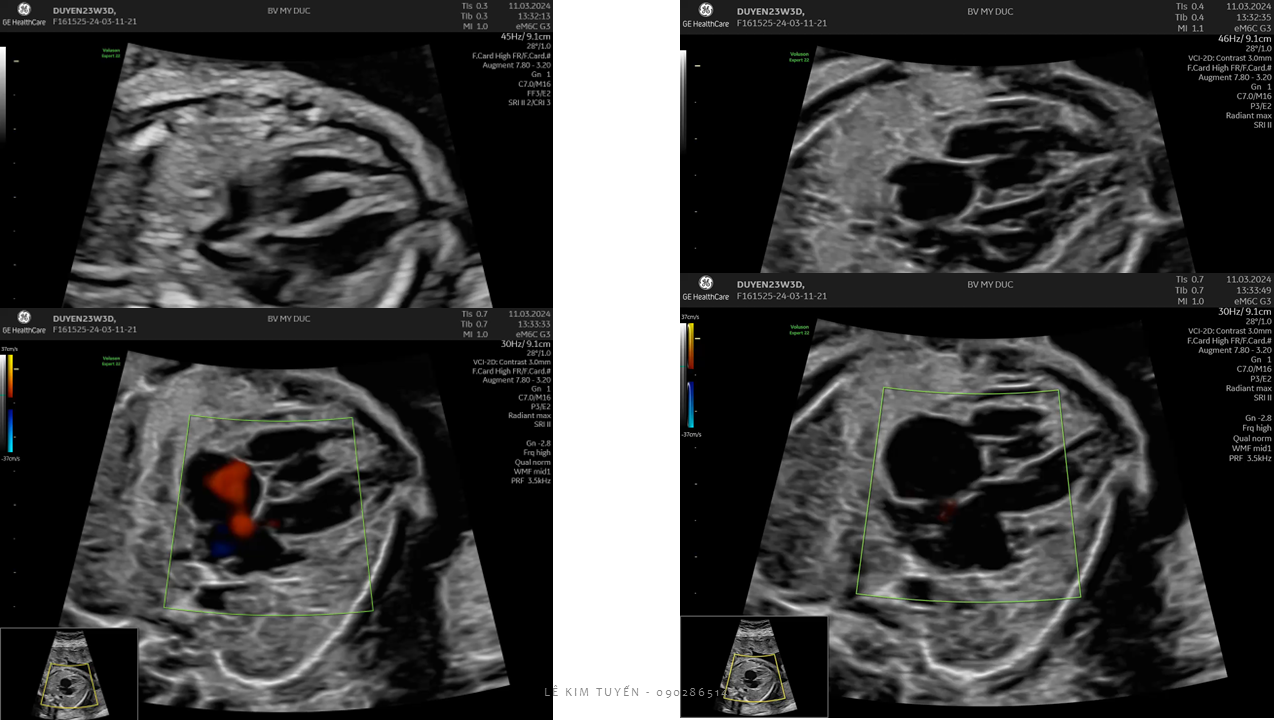

Siêu âm tim thai - Các kỹ thuật hiện đại

TS. BS. Lê Kim Tuyến

Bệnh viện Tim Tâm Đức